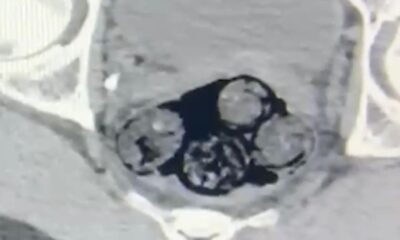

İl Emniyet Müdürlüğü Narkotik Suçlarla Mücadele Şube Müdürlüğünün yurt dışından Türkiyeye vücutlarında uyuşturucu sokanlara yönelik yaptığı çalışmada gözaltına alınan yabancı uyruklu kişi hastaneye götürüldü. Radyolojik görüntüleme...